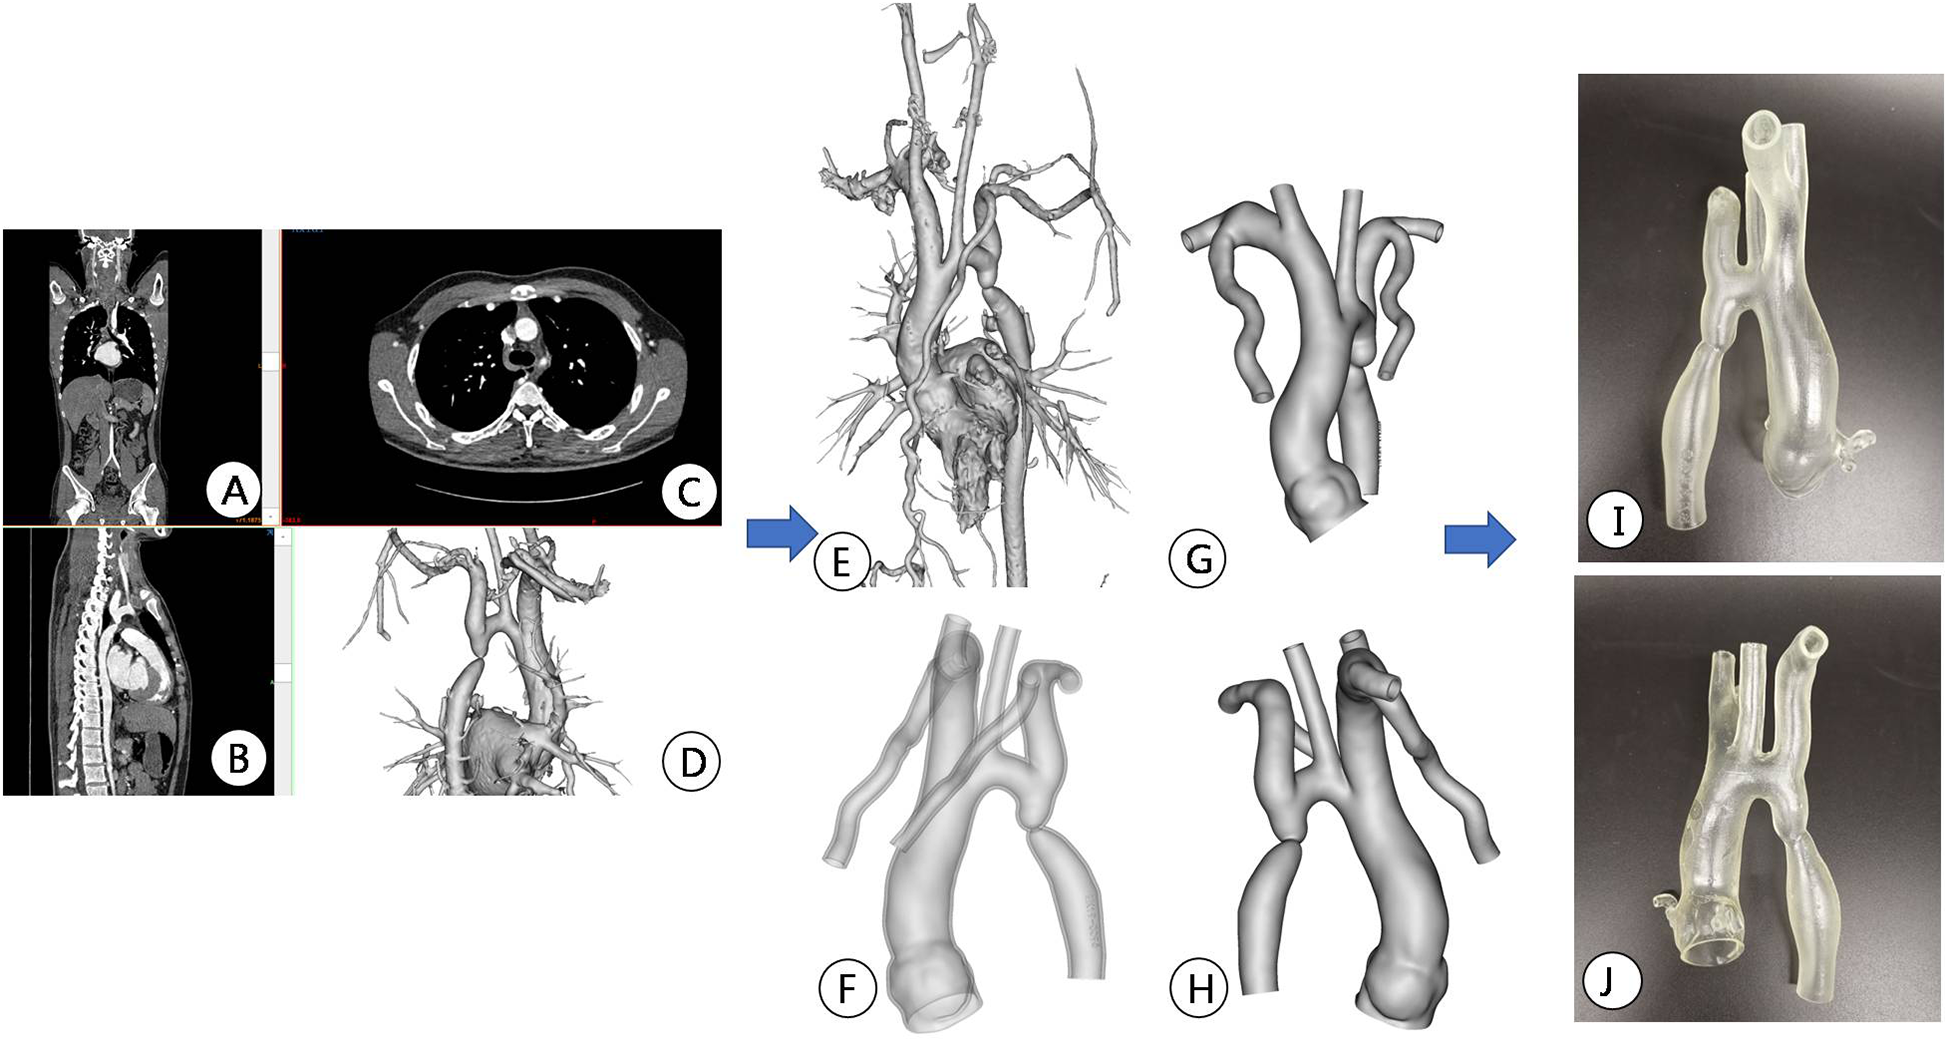

Figure 3

Preoperative CT image data reconstruction and 3D printing model of patients. (A–C) Display CTA images of the aorta in different sections; (D,E) Mimics software displays the location of active artery constriction at different angles after reconstruction; (F–H) segmentation, decoration, and reconstruction of images for subsequent 3D printing; (I,J) 3D printed aortic constriction model displayed on different sides.